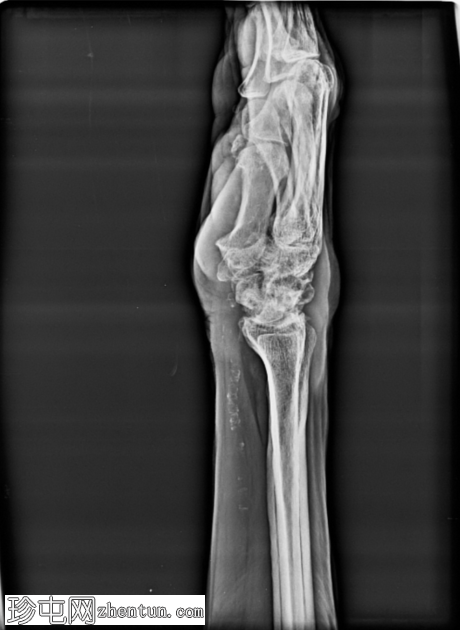

X线片

正位片

侧位片

腕关节明显退行性改变,腕骨排列异常。舟月间隙增宽,符合舟月韧带功能不全的表现。头状骨近端移位。桡腕关节间隙明显狭窄,软骨下硬化,边缘骨赘形成。远端桡尺关节也可见退行性改变。腕骨、桡骨远端和尺骨均可见骨质疏松。未见急性骨折或脱位。